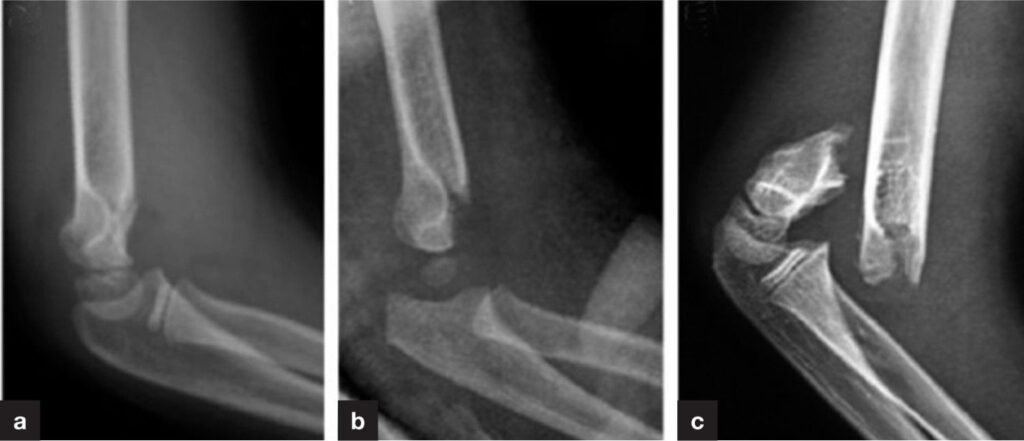

A supracondylar fracture occurs just above the elbow joint in the humerus bone. This type of injury can affect nerve and blood vessel function if not managed correctly. At centers offering the Best Supracondylar Fracture Treatment in Udyog Vihar, accurate assessment is the first step toward successful recovery.

Clinical examination and imaging studies help determine fracture type, displacement, and severity.

Closed Reduction Techniques for Displaced Fractures

When fracture fragments are displaced, closed reduction may be required. Under the Best Supracondylar Fracture Treatment in Udyog Vihar, careful manipulation is performed to realign the bone without making surgical incisions.

Surgical Treatment for Complex Supracondylar Fractures

Severely displaced or unstable fractures often require surgical intervention. The Best Supracondylar Fracture Treatment in Udyog Vihar includes advanced surgical techniques that stabilize the fracture using pins or fixation devices.